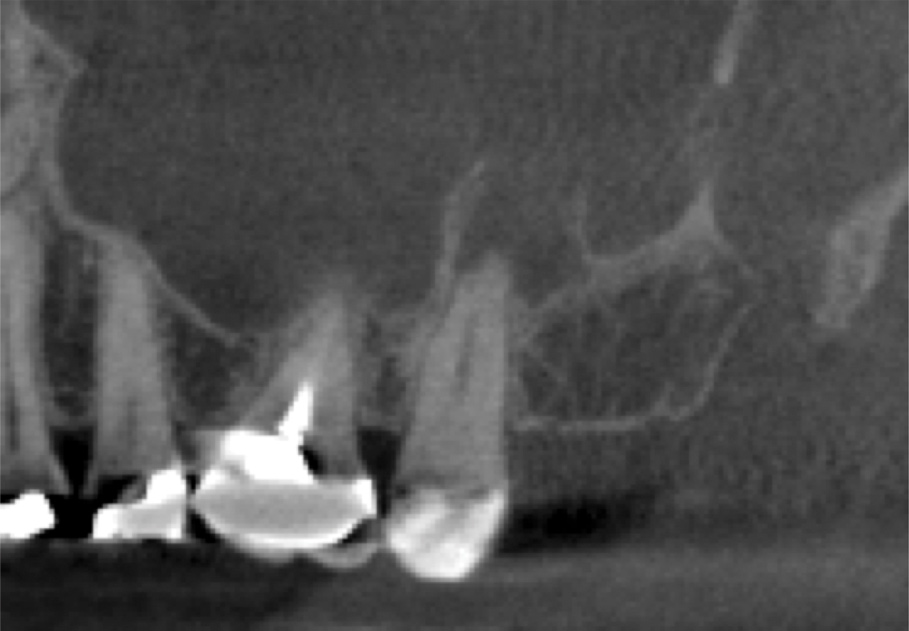

A 58-year-old female patient presented to the office with a 3-month history of acute sinusitis, during which six courses of antibiotics, including penicillin, cephalosporin, and quinolone drugs, had failed to resolve her symptoms. She had been referred for endodontic evaluation by her ENT specialist after imaging revealed endodontic pathosis of tooth No. 2. On initial presentation, tooth No. 2 was nonvital (ie, nonresponsive to cold or electric pulp testing), tested positive to percussion and palpation, and was without swelling, sinus tracts, or periodontal defects. The preoperative CBCT scan revealed apical pathosis on the buccal and palatal roots of tooth No. 2, complete opacification of the right maxillary and ethmoid sinuses, and disruption of the lateral/posterior antral wall posterior to the zygomaticomaxillary buttress (Figure 6). Root canal therapy was initiated. Upon access, black staining of the pulp tissue was observed, indicating necrosis. Pulpal debridement was performed, and calcium hydroxide was utilized as an intracanal medication. Several weeks after pulpal debridement, the patient's sinus symptoms improved, but incompletely. Tooth No. 2 was obturated, and the patient was referred to an ENT specialist for further care.

Three months after NSRCT and one month after FESS, she returned to her endodontist for a follow-up appointment. She reported experiencing only minor sinus pressure, which she believed to be attributed to seasonal allergies. Upon examination, no swelling, mobility, or sinus tracts were noted, and tooth No. 2 was not tender to percussion or palpation. CBCT imaging revealed both clearing of the sinus and initial healing of the apical pathosis (Figure 7 and Figure 8). Continued follow-up appointments were recommended.

This case demonstrates a typical presentation of MSEO, in which an apical radiolucency obliterated the cortical bone of the sinus, causing a direct communication between the two structures. NSRCT was used to treat the dental etiology and following resolution of the apical pathosis, resulted in the restoration of the cortical boundary between the root apex and maxillary sinus. The severity of the pathosis necessitated significant sinus treatment to achieve resolution, including dental, medical, and surgical interventions.

(6.) Preoperative CBCT image showing periapical pathosis of tooth No. 2 in communication with the sinus.

Figure 6

(7.) Postoperative CBCT images taken 3 months after NSRCT (ie, 6 weeks after sinus surgery), showing sinus clearing and reduction in the size of the PAO lesion.

Figure 7

(8.) Postoperative CBCT images taken 3 months after NSRCT (ie, 6 weeks after sinus surgery), showing sinus clearing and reduction in the size of the PAO lesion.